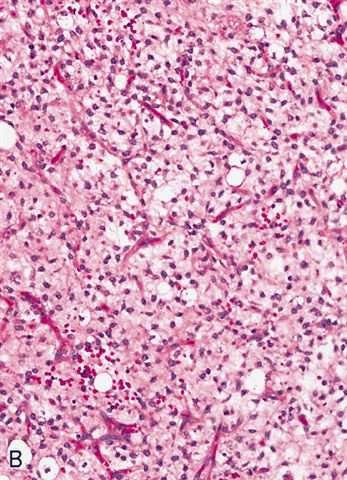

- High grade

- Hypercellular solid sheets of back to back cells with round cell or primitive cytomorphology in > 5% of the sampled tumor

- Cells can have a small amount of hypereosinophilic cytoplasm, a finding of no clinical significance but of significant diagnostic confusion, especially in a limited sample

- High grade tumors are so cellular that you can typically walk across nuclei in a high power field without stepping in matrix